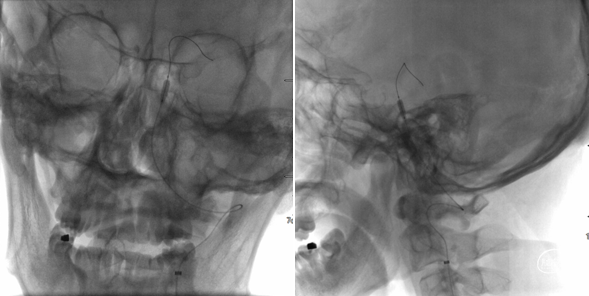

头CT(急诊):左侧小脑半球、左侧放射冠、半卵圆中心、额顶枕叶脑梗死。

头颈CTA :左侧颈内动脉末端及基底动脉重度狭窄或闭塞。

术前CT,ASPECT 8分。

术前CTA检查。